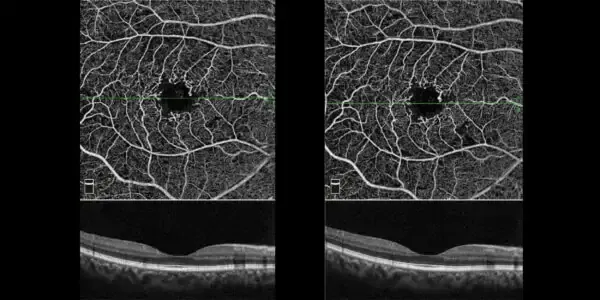

Avec le scanner OCT rétine haute définition, explorez les avantages de la plateforme Optovue Solix à Paris, Marseille et Lyon. Grâce à sa technologie FullRange®, obtenez une visualisation détaillée, de la cornée à la chambre antérieure, en un seul scan. Cet appareil OCT innovant permet une analyse complète, idéale pour le diagnostic précoce et le suivi des anomalies rétiniennes.

Optez pour un outil aussi performant que l’

Optovue Solix, combinant précision et rapidité afin d’obtenir une imagerie rétinienne fiable et des résultats optimaux.